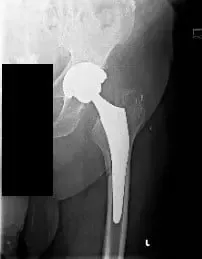

Radiografía preoperatoria de la cadera izquierda vista AP que muestra una fractura femoral periprotésica (desplazada mínimamente a lo largo de la parte medial del miembro femoral proximal) con hundimiento del tallo.